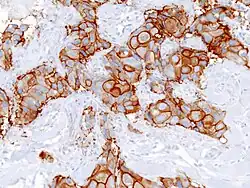

- Immunohistochemistry – the use of antibodies to detect the presence, abundance, and localization of specific proteins. This technique is critical to distinguishing between disorders with similar morphology, as well as characterizing the molecular properties of certain cancers.